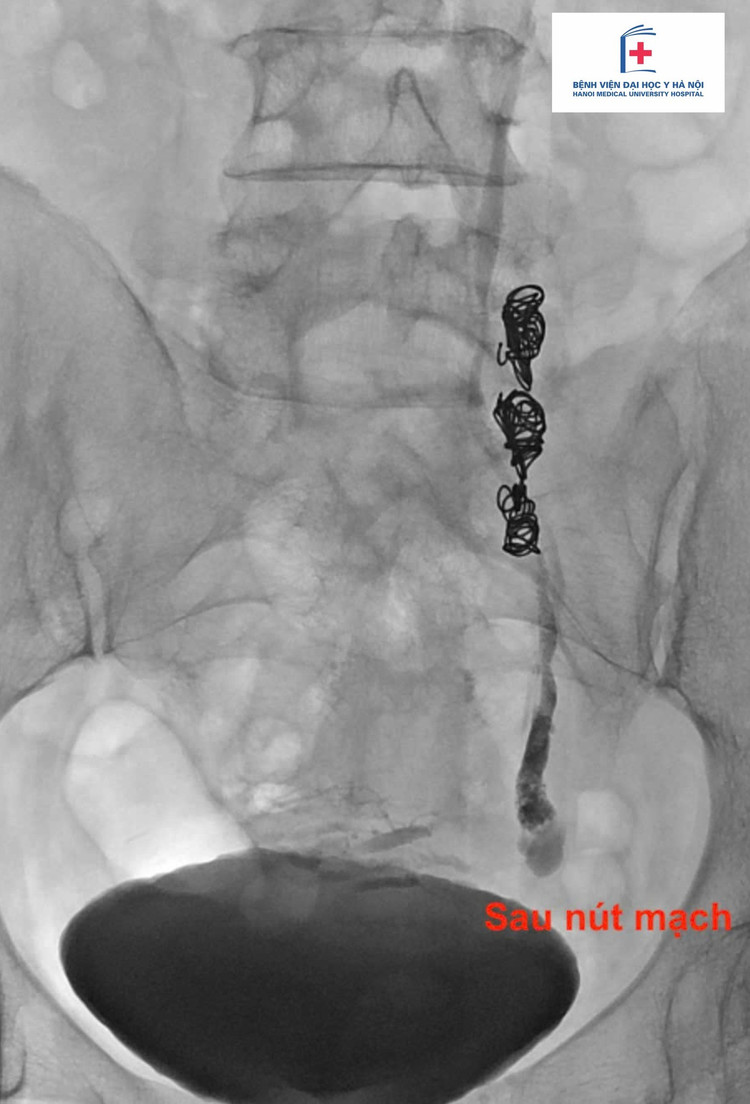

Chẩn đoán được xác định thông qua siêu âm ổ bụng và chụp CT có tiêm thuốc cản quang. Các bác sĩ đã giải thích, tư vấn cho người bệnh về điều trị bằng phương pháp nút mạch qua da - sử dụng dụng cụ can thiệp để bít tắc các tĩnh mạch giãn bất thường, ngăn dòng máu trào ngược gây đau. Sau can thiệp, triệu chứng đau giảm rõ rệt, người bệnh phục hồi nhanh chóng.

506287183-1189359819902131-6831978309968155435-n.jpg

Ảnh BSCC